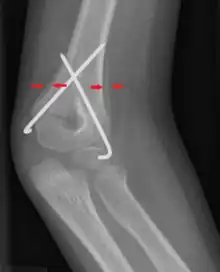

Periosteal reaction on a healing supracondylar fracture

A periosteal reaction is the formation of new bone in response to injury or other stimuli of the periosteum surrounding the bone.[1] It is most often identified on X-ray films of the bones.